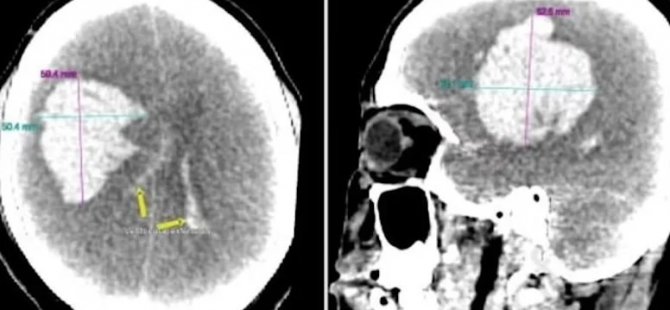

Bilim insanları ve uzmanlar, adamın beyninde serebrovasküler kanama meydana geldiği belirtilirken damarların patladığı kayıtlara geçti. Yapılan otopsi taramalarında adamın beyninde 300 gram kan pıhtısı oluştuğu açıklandı. Patologlar, adamın yaşadığı rahatsızlığın alkol ve ilacın etkisi olduğunu öne sürerken, “Damarlarında daha önce de görülen düzensizlik ile birlikte kanama gerçekleşmiş olabilir” dedi.